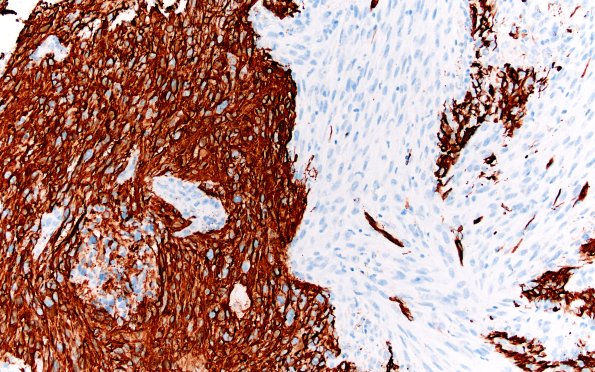

23A11 Gliosarcoma (Case 23) GFAP Area B 20X 1

GFAP stained area 23A10